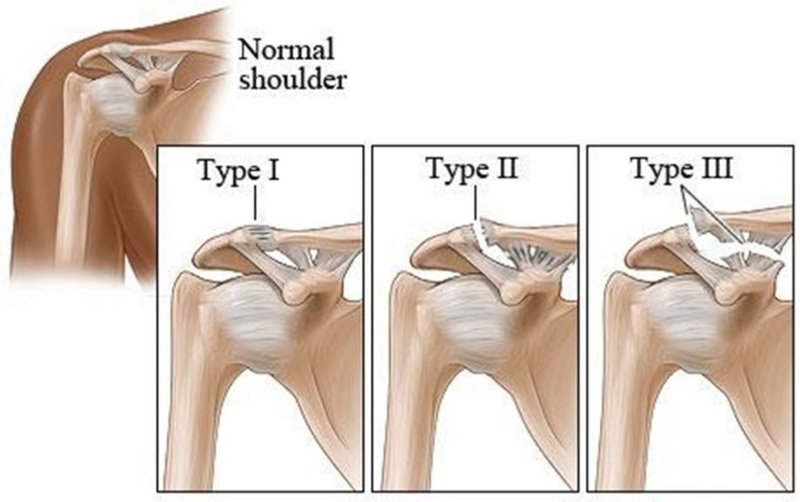

肩鎖関節脱臼(けんさかんせつだっきゅう)とは、鎖骨と肩甲骨の肩峰(けんぽう)との間にある 肩鎖関節 と呼ばれる関節が正常な位置からずれてしまった状態のことです。 ラグビーや柔道、アメリカンフットボールなどのコンタクトスポーツ、交通事故や 手術記録テンプレート:肩関節脱臼〜Bankart法〜 年12月5日 全身麻酔下に関節の動揺性を確認し、前下方の動揺性を認めた。 3 portal 前後ポータル作成し手術開始。 以下の所見を得た。 PATHOLOGY Synovitis:RI()LHB () axillary pouch()5月日 ついに手術である;_; 日帰りの肩の手術の詳細は 以下の通り 当日、麻酔科の看護師さんにもらった 出来れば予約した時にもらいたかったよぉ 難治性五十肩に対する非観血的授動術 (マニプレーション) マニピュレーションとは、肩と腕に麻酔を行い、 知人で小さくなっている関節包を広げる方法です。

さらさんのブログテーマ、「反復性肩関節脱臼」の記事一覧ページです。 反復性肩関節脱臼|Saraの脱臼手術とテニスと美容 ホーム ピグ アメブロ 保存療法は三角筋などによる固定で十分であり、過度な固定はしないように注意が必要です。 それよりも、痛みの軽減に合わせて早い時期から関節を動かすように努めることが大切です。 手術が必要な場合には、烏口鎖骨靭帯の再建術として「Cadenat法」や「Dewar法」、肩鎖靭帯再建術として「Neviaser法」などが普及しています。 また、肩鎖関節周囲の関節や肩甲骨反復性肩関節脱臼の手術 肩関節は反復性脱臼が最も多くみられる関節です。ほとんどのものが外傷性の脱臼 に続発しておこります。外傷による肩関節の脱臼は、ラグビー、アメフト、柔道など のコンタクトスポーツに多く、前下方脱臼がほとんどです。